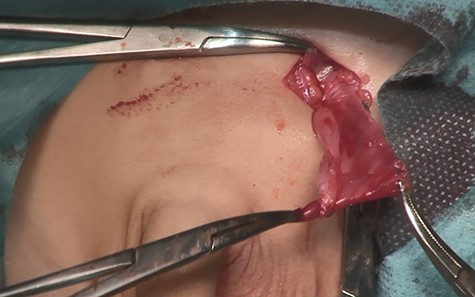

A14-month-old boy was admitted to our hospital to undergo inguinal orchidopexy. At the age of 1 month, the left testis was palpable between the inguinal canal and the scrotum. When he was 6 months old, ultrasonography showed the left testis inside the inguinal canal (Fig. 1). At the age of 13 months, the patient was seen in the outpatient clinic for preoperative examination in preparation for inguinal orchidopexy; the left testis was not palpable at that time. At the age of 14 months, we began surgery with a preoperative diagnosis of an undescended testis. When the inguinal canal was opened, only a patent processus vaginalis was visible (Fig. 2). After incision of the membrane, we were able to retrieve the testis from the abdominal cavity (Fig. 3a). The patent processus vaginalis was closed, a dartos pouch was created and the testis was guided into the pouch and fixed to its wall (Fig. 3b).

Intraoperative photography (14 months of age). After opening the inguinal canal, only a patent processus vaginalis is visible.